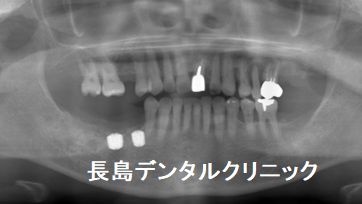

2、抜歯と同時にインプラントを埋入

インプラントの径は8ミリと7ミリです。長さは両方7ミリです。この

位の太いインプラントが入れば、長いインプラントは必要ありませんし

より安全にインプラントを埋入することにつながります。